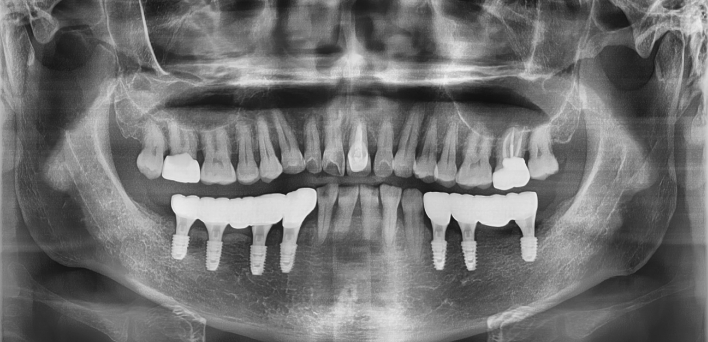

임플란트 : 손 ** 님 (50대)

치아가 있다는게, 아직도 정말 꿈만 같아요.

Before Before

2020.02.30

After After

환자 특징01무치악 상태

환자 특징02수년간 무치악으로 지내심

임플란트가 불가능할것이라

생각하고 내원

위, 아래 6개씩 식립

디지털 풀아치 임플란트